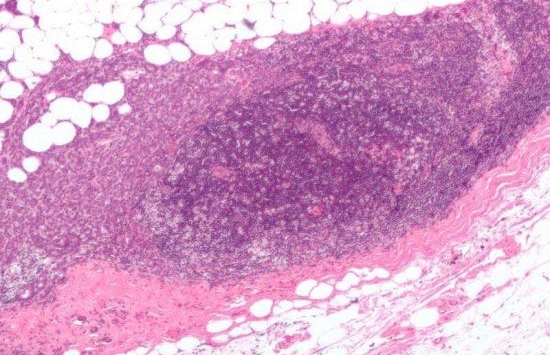

![]() |

| Ảnh minh họa |